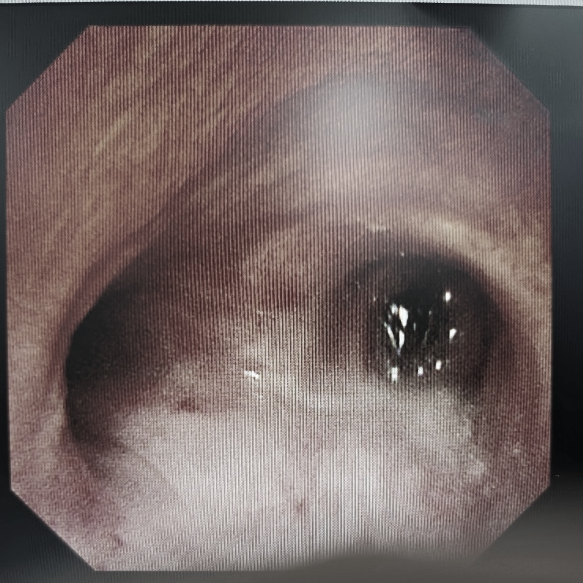

刘亭威立即再经电圈套器套切,新生物基本切除,可见新生物残端位于左下叶基底段开口,以氩气刀喷灼残端,吸除左主支气管内溢出的大量分泌物,手术历时近1小时顺利结束,患者大气道梗阻得到充分缓解。

术后患者主气管及左主支气管阻塞完全开通,组织瓶内为切除的大量肿物组织